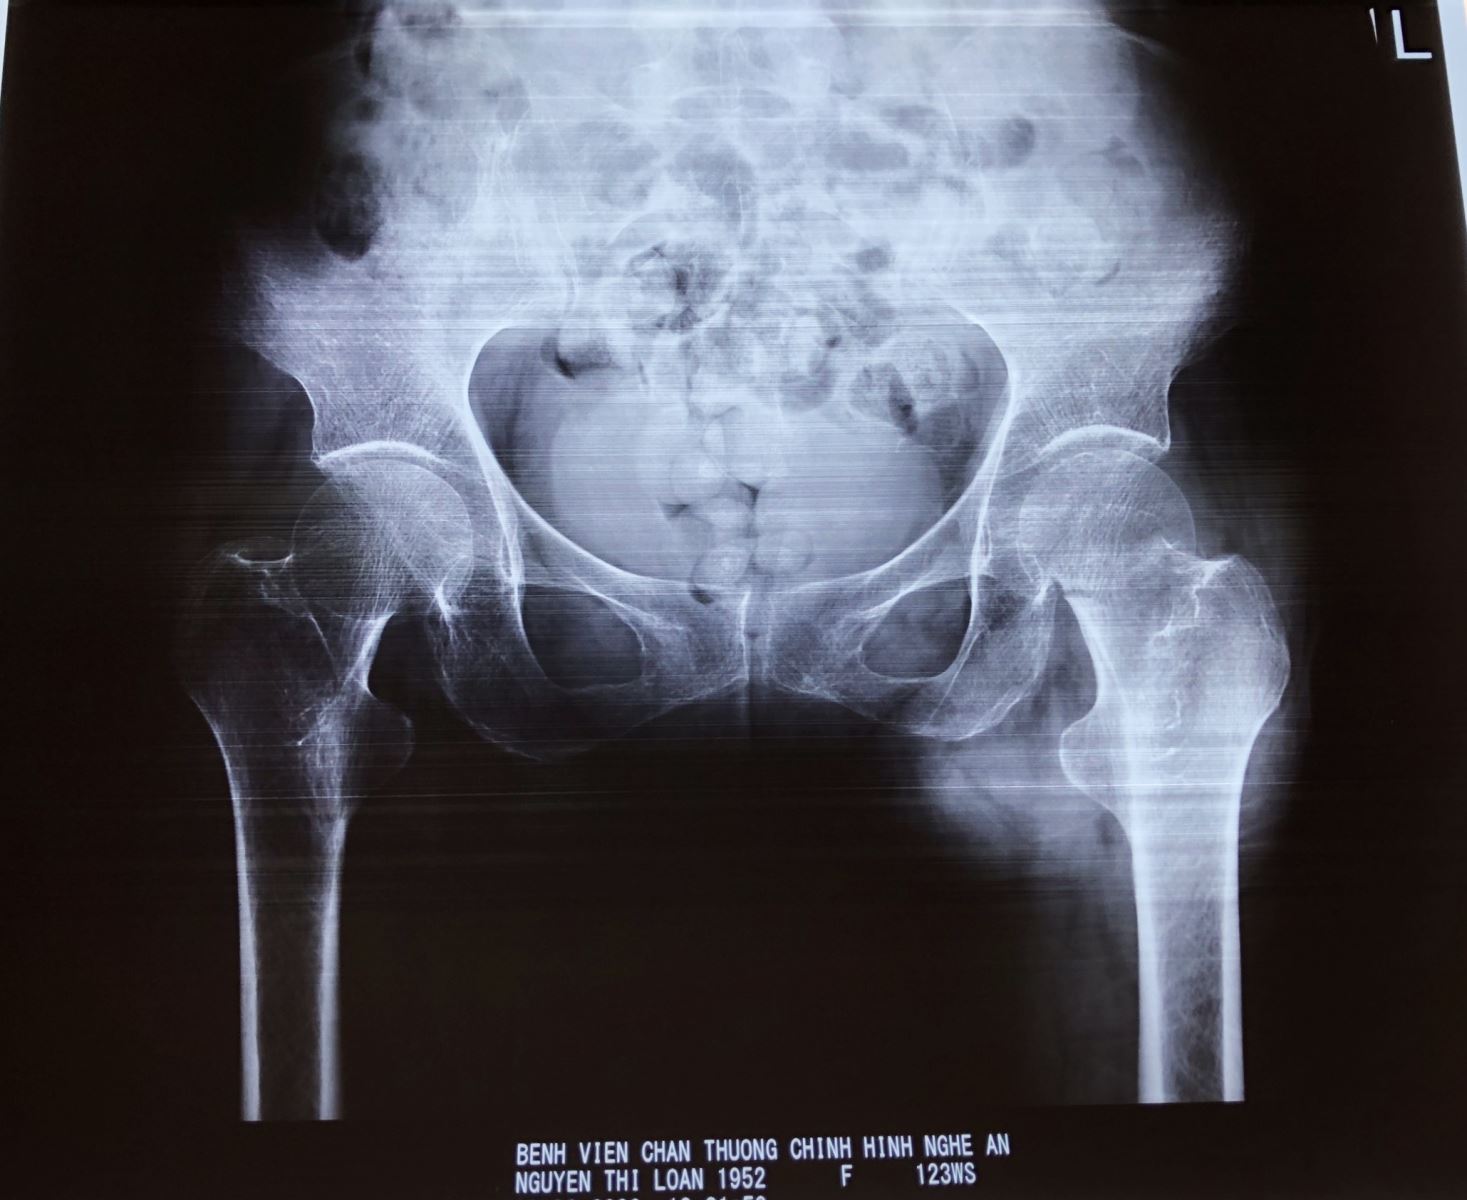

Bệnh nhân Nguyễn Thị Loan, 68 tuổi, ở TP.Vinh – Nghệ An có tiền sử  parkinson, đã điều trị 6 năm nay. Đợt này bệnh nhân trượt chân ngã gây đau biến dạng, hạn chế vận động đùi háng trái. Vào Bệnh viện Chấn thương Chỉnh hình Nghệ An, bệnh nhân được chẩn đoán gãy cổ xương đùi trái.

Hình ảnh phim chụp Xquang của bệnh nhân trước và sau phẫu thuật thay khớp háng